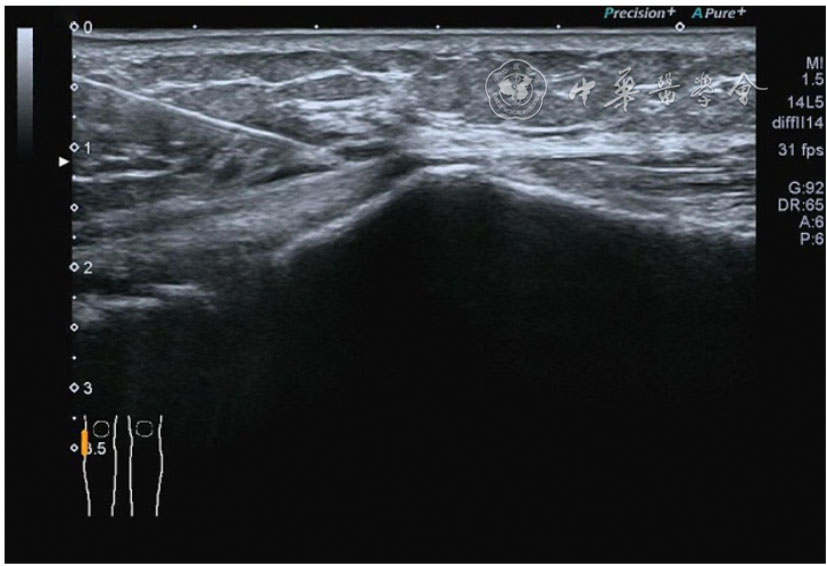

2.膝关节静态结构治疗。动力平衡失调后,继发静态结构变化,出现内外侧副韧带、交叉韧带、脂肪垫、半月板等结构变化。这里介绍半月板与交叉韧带的处理。(1)膝关节静态结构半月板治疗。在膝关节骨关节炎中主要是突出和损伤。突出主要发生于膝内翻引起的内侧半月板突出,引起内侧副韧带的张力增高。内侧半月板与内侧副韧带相连,是引起膝关节内侧疼痛的主要原因之一。治疗主要是针刀剥离松解,部分损伤可行PRP注射。①半月板突出针刀剥离松解治疗。针刀治疗主要是松解和减压,缓解疼痛,不能复位。以内侧半月板突出治疗为例。患者平卧位,髋轻度外展外旋,膝关节屈曲30°,膝下垫一软枕。选用10 MHz超声探头,穿刺区域常规消毒,探头涂抹耦合剂后套入无菌手套碘伏消毒或使用无菌耦合剂。将探头置于患者皮肤表面,内侧关节间隙长轴扫查,找到半月板突出最高点,用25G针头,抽吸1%利多卡因3 ml逐层麻醉直到半月板。选用直径1 mm的Ⅰ型2号针刀从头侧向足侧方向在内侧副韧带与半月板之间,以及半月板内部进行剥离松解3~5刀拔出针刀(图13),局部压迫5分钟,无菌敷料覆盖。②半月板损伤PRP注射治疗。半月板损伤主要表现为髌下痛,伸膝加重,查体在髌下髌韧带与侧副韧带之间,沿关节间隙有固定或局限性压痛,伸膝过程中尤为明显。MRI可示半月板断裂、损伤。如果出现绞索,严重影响功能需手术治疗。半月板损伤治疗,以注射PRP修复为主。以内侧半月板后角损伤为例。患者俯卧位,治疗前准备同半月板突出针刀剥离松解治疗。选用25G注射针头,抽取1%利多卡因2 ml局部麻醉后,制取1.5 ml PRP,穿刺到达半月板撕裂处注射,注射完毕后出针(图14),局部压迫2分钟,无菌敷料覆盖。(2)膝关节静态结构交叉韧带治疗。膝关节骨关节炎交叉韧带损伤多为部分损伤,治疗早期主要为药物或PRP注射,效果不佳时针刀做止点松解。①后交叉韧带损伤药物注射治疗。主要治疗韧带肿胀、无明显断裂患者。患者俯卧位,膝关节伸直位。一般选用10 MHz超声探头,治疗前准备同半月板突出针刀剥离松解治疗。将探头置于患者皮肤表面,后交叉韧带长轴扫查,找到胫骨止点,选用22G长针头,抽吸1%利多卡因3 ml+曲安奈德10 mg,从头侧向足侧方向穿刺到后交叉韧带胫骨止点部位的韧带表面进行注射,注射结束拔出针头(图15),局部压迫2分钟,无菌敷料覆盖。②前交叉韧带损伤PRP注射治疗。患者仰卧位,膝关节伸直。选用10 MHz超声探头,治疗前准备同半月板突出针刀剥离松解治疗。将探头置于患者皮肤表面,短轴扫查,找到前交叉韧带胫骨止点,选用25G针头,抽吸1%利多卡因3 ml逐层麻醉直到韧带止点部位,制备PRP 3 ml注射到前交叉韧带显露部位,注射结束拔出针头(图16),局部压迫2分钟,无菌敷料覆盖。③前交叉韧带损伤针刀剥离松解治疗。体位与治疗前准备同前交叉韧带损伤PRP注射治疗。短轴扫查找到前交叉韧带胫骨止点,选用25G针头,抽吸1%利多卡因3 ml逐层麻醉直到韧带止点部位,选用直径0.6 mm的Ⅰ型2号针刀从外侧向内侧于前交叉韧带胫骨止点部位剥离松解3~5刀拔出针刀(图17),局部压迫5分钟,无菌敷料覆盖。

图15 超声引导下后交叉韧带损伤药物注射治疗